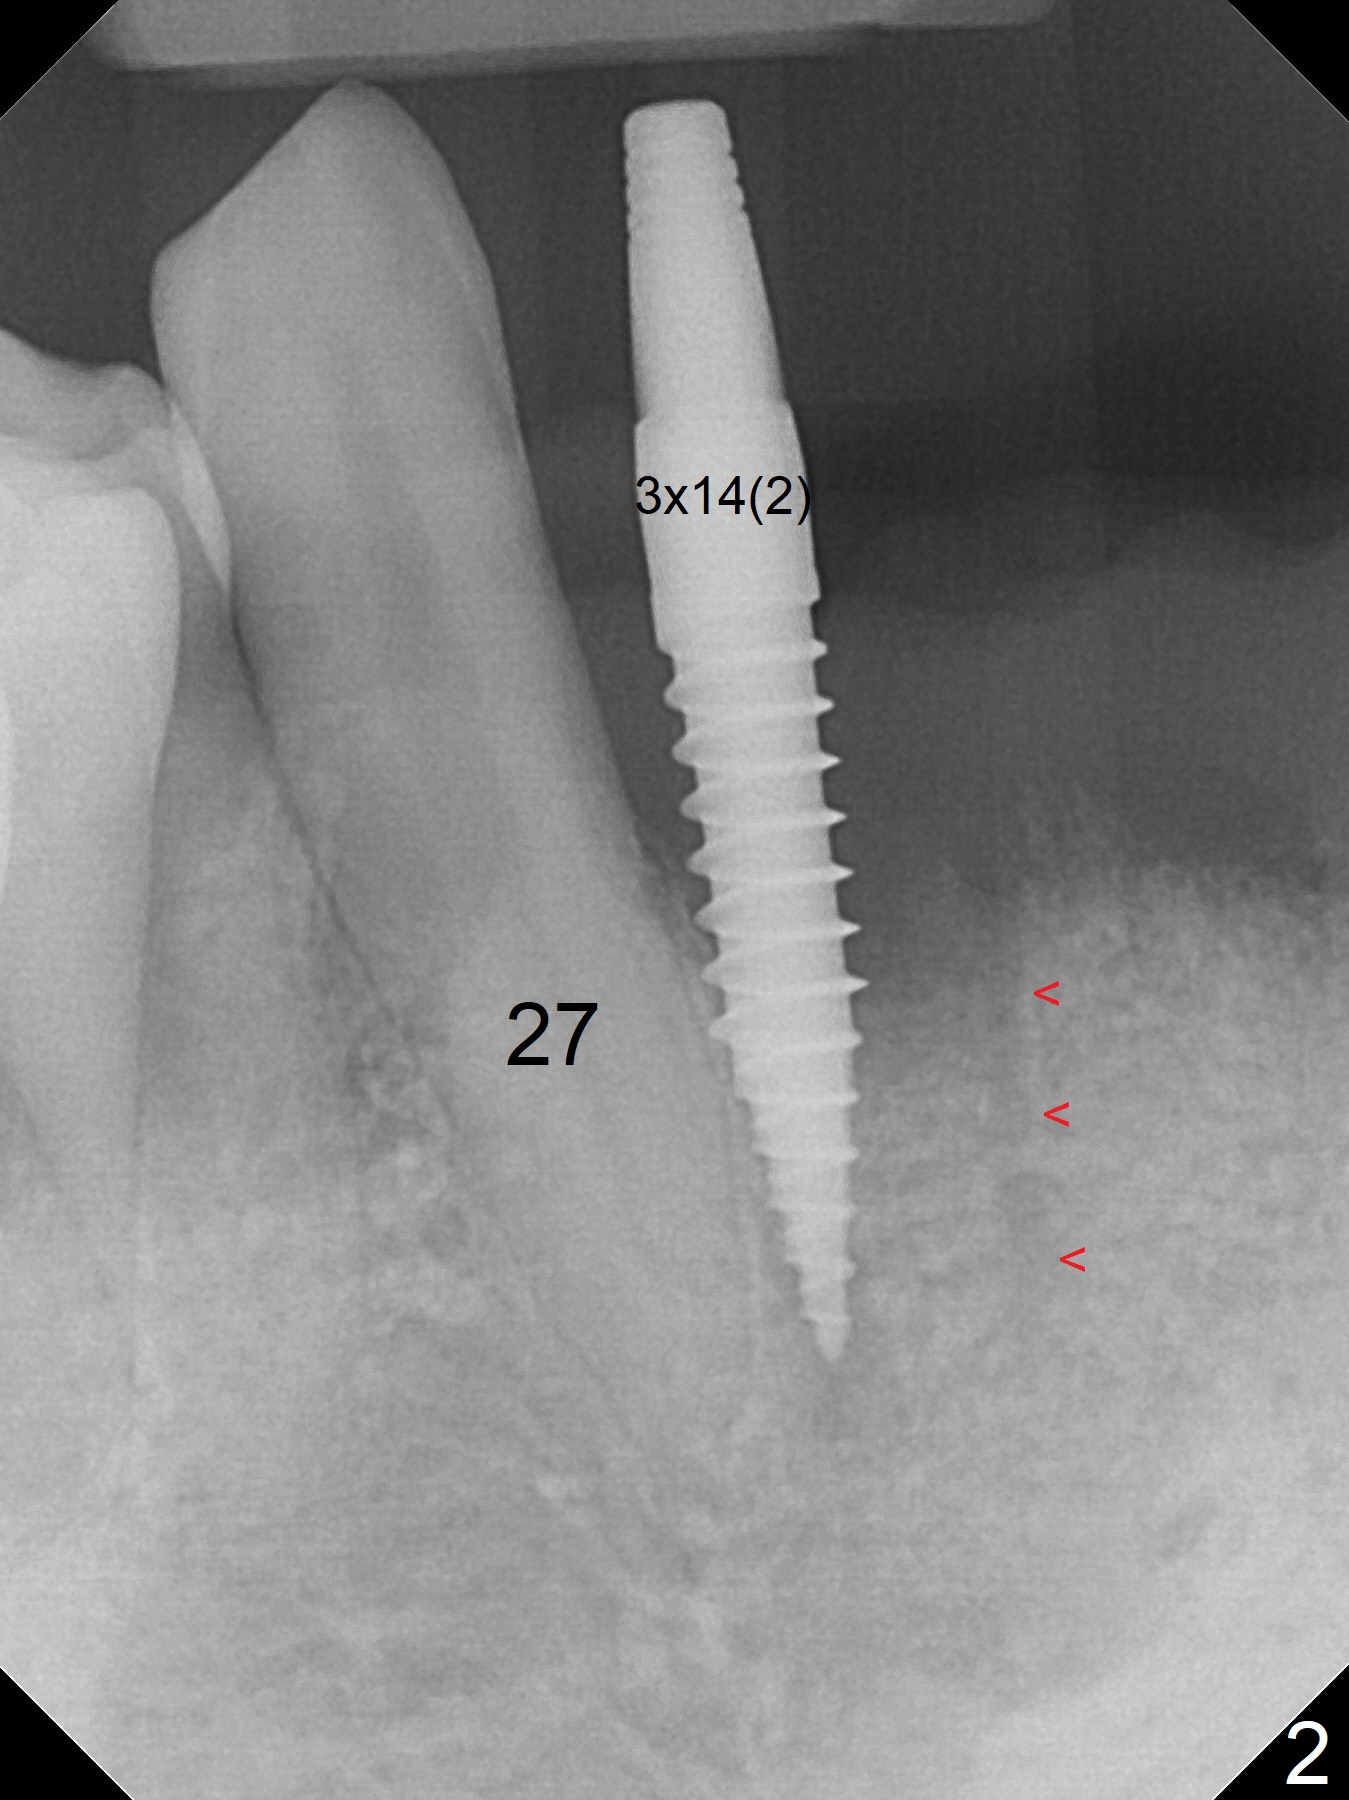

After extraction of 4 of the lower incisors, there are basically 2 sockets (#23/24 and 25/26), separated by the apparently midline bone (Fig.1 red line). In spite of using Lindamann bur to move the 25/26 osteotomy mesially, a 3x14(2) mm dummy implant remains close to the tooth #27 (Fig.2). The terminal branch of the Incisive Canal (<) is located between the lateral and central incisors. A de novo osteotomy (Fig.3 (1.5 mm drill)) is made mesial to the original one (O). While the 3x14(2) mm dummy implant is incompletely placed at #25/26, a 3x14(4) mm 1-piece one is placed at #23/24 (Fig.4). Finally the same implant is placed at #25/26 with placement of mineralized cortical/cancellous bone (Fig.5 *). When the large sockets are sutured, the supraerupted teeth #7-9 touch the lower gingiva (Fig.6). The incisal edge is reduced for clearance (Fig.7). Periodontal dressing is less likely to be dislodged with the incisal edge reduction (Fig.8,9). A provisional FPD is fabricated 1 week postop. Hard (Fig.10) and soft (Fig.11,12) tissues heal 5.5 months postop. The patient returns for crown cementation 3 months post impression (9 months postop, Fig.13,14).